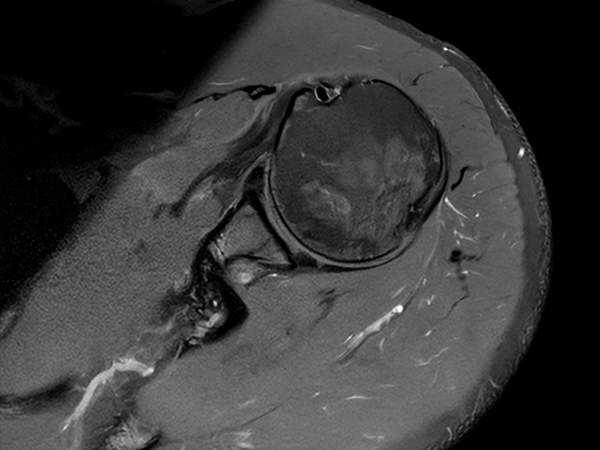

High quality Shoulder imaging with SmartSpeed Precise